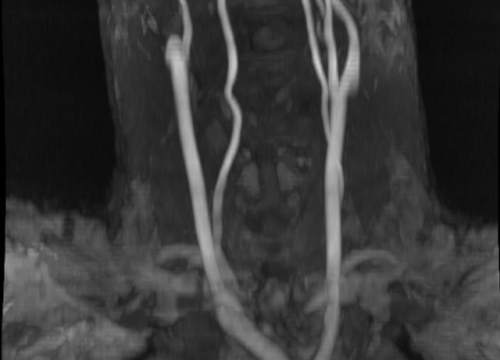

Svjetski dan zdravlja: Ateroskleroza svjetski ubojica broj jedan

Povodom svjetskog dana zdravlja o aterosklerozi kao najvećim javnozdravstvenim problemom i vodećim uzrokom bolesti i smrti na svijetu, pričali smo s doktorom specijalistom neurologije dr.